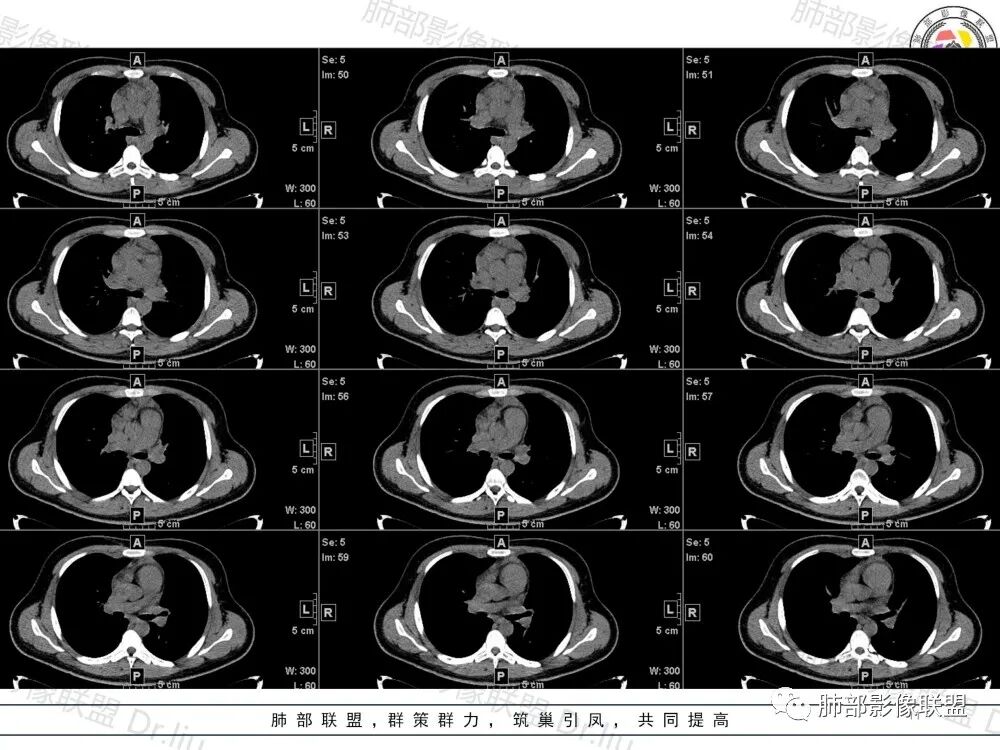

1、临床特点:19岁男性,发现双肺结节,实验室检查无特殊。

2、影像特点:两肺可见多发大小不一的结节影,部分结节周围可见晕征,部分结节沿着支气管血管束分布,部分位于胸膜下。前纵隔内可见多发结节样软组织密度影,边界不清,部分病灶融合倾向,其脂肪间隙显示模糊。由于腹腔层面少,未能确定腹腔内有无增大淋巴结,需要连续层面追踪观察。

3、病例小结:年轻男性+前纵隔多发结节样软组织影+双肺多发结节,需要警惕淋巴瘤,至于多数老师提到鉴别结节病,结节病以双肺门对称性淋巴结肿大为典型表现,其肺内表现多为沿肺门旁支气管血管周围间质分布的多发结节,结节病可表现纵隔内多发淋巴结肿大、且淋巴结密实,孤立少融合,该病例中均缺乏以上特点,另外结节病好发中青年女性,此病例年龄亦不符合。